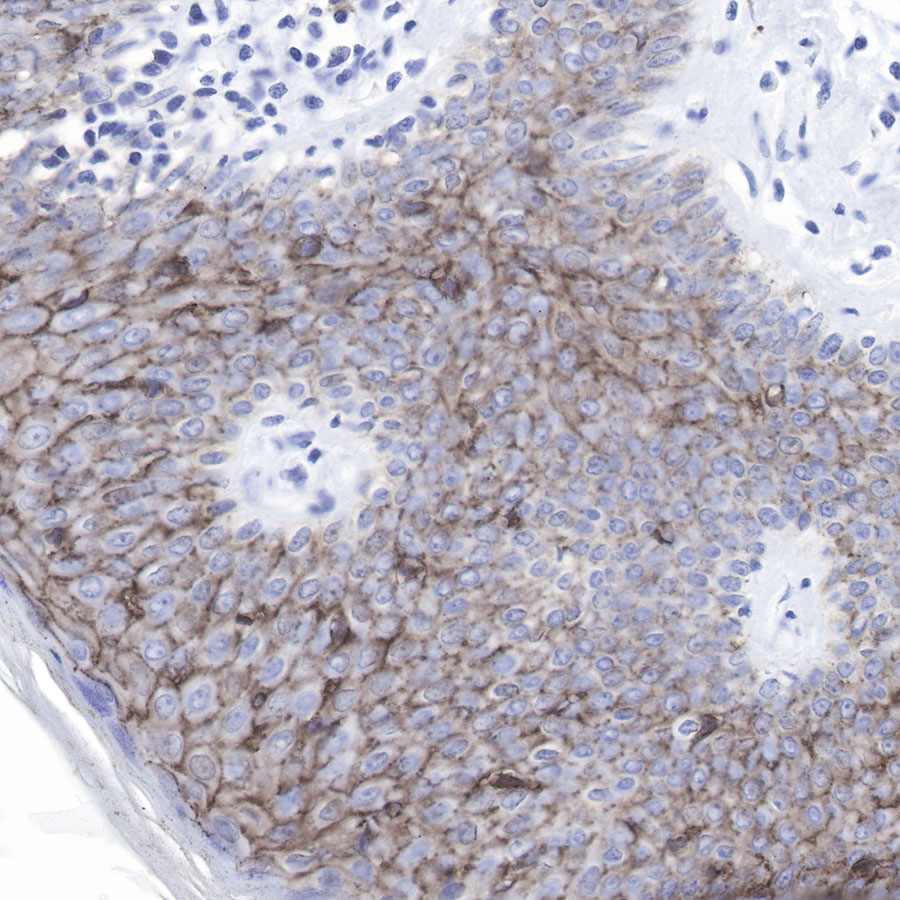

IHC shows positive staining in paraffin-embedded human tonsil.

Anti-Claudin-1 antibody was used at 1/500 dilution, followed by a Goat Anti-Rabbit IgG H&L (HRP) ready to use. Counterstained with hematoxylin.

Heat mediated antigen retrieval with Tris/EDTA buffer pH9.0 was performed before commencing with IHC staining protocol.